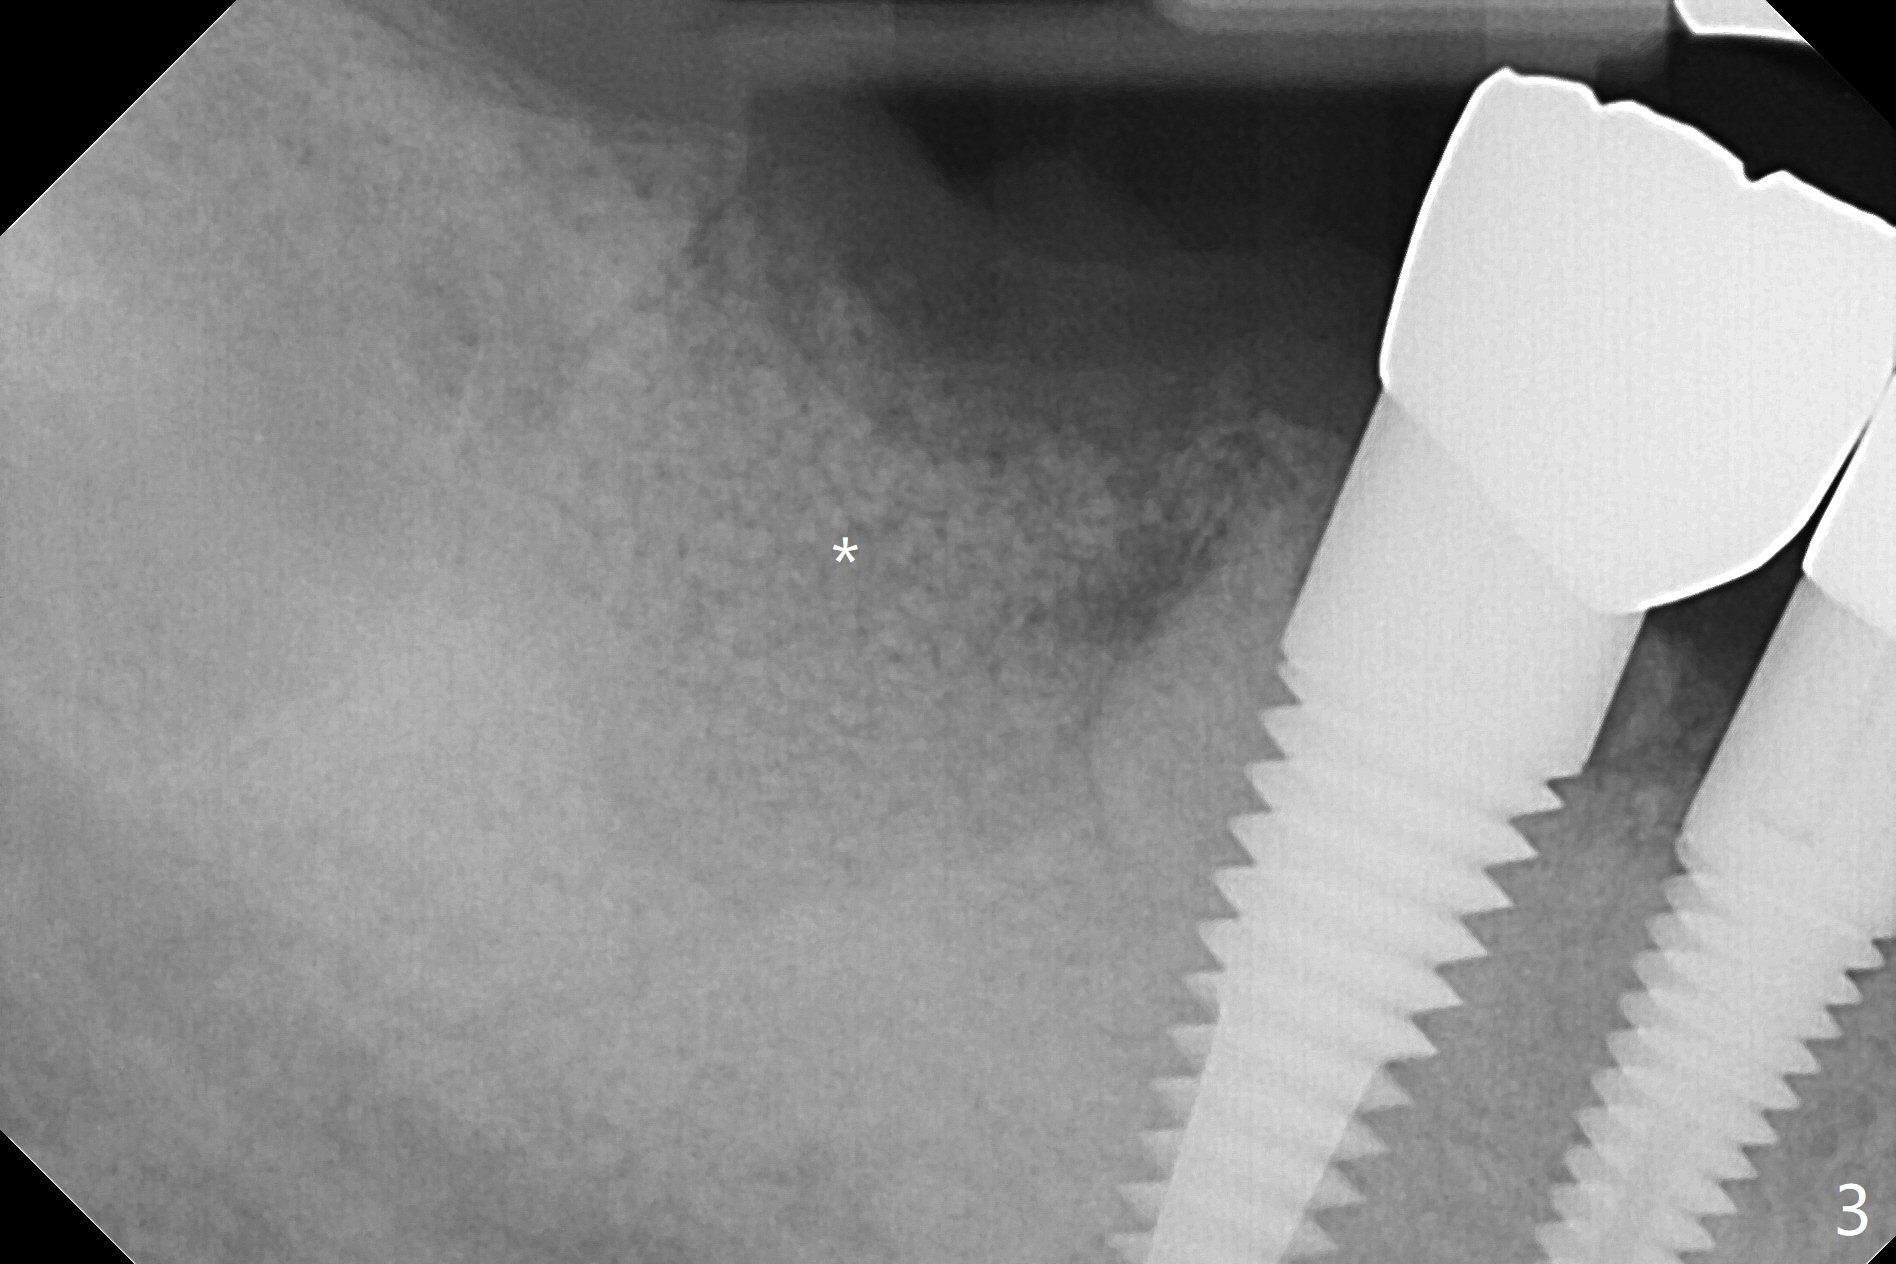

A 88-year-old man returns with pain and swelling (Fig.1), one year after diagnosis of #31 mesial root fracture. After discussion, the tooth is extracted with socket preservation (Vanilla graft mixed with Osteogen, covered with Osteogen plug and Collagen plug, Fig.2,3). The buccal crest is much lower than the lingual one. The socket opening reduces with resolution of 4-0 Chromic gut suture 1 week postop (Fig.4). The wound is wider with foul odor 2 weeks postop (data not shown). The socket and ridge shrink with loss of the bone graft 3 weeks postop (Fig.5). The bone volume reduces with buccal plate collapse 3 months postop (Fig.6,7). Immediate implant and provisional should be able to help restore the lost buccal plate. The buccal plate remains concave 5 months postop (Fig.8,9). The coronal section shows that there is space (Fig.10 *) buccal to the graft (G). A 2.0 mm pilot drill is used to create an initial osteotomy through the graft zone and in the beginning of the native bone (Fig.11,12). Use bone expanders (Fig.13 E) to push (arrowheads) and condense the graft bone and close the buccal gap. The apical portion of the osteotomy requires regular drills (Fig.14 D).